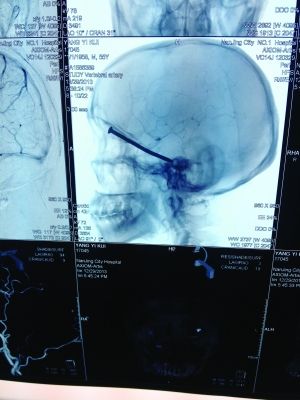

CT投影

CT投影結果,把大家嚇了一跳:楊先生腦子里居然有一根長釘,從眼眶一直“伸”到了接近后腦勺的位置!鐵釘細長略帶彎曲,長達8厘米。根據(jù)推測,鐵釘應該是從上眼眶的縫隙中飛入,一直插進腦顱中,末端還有一個小小凸出的釘帽。